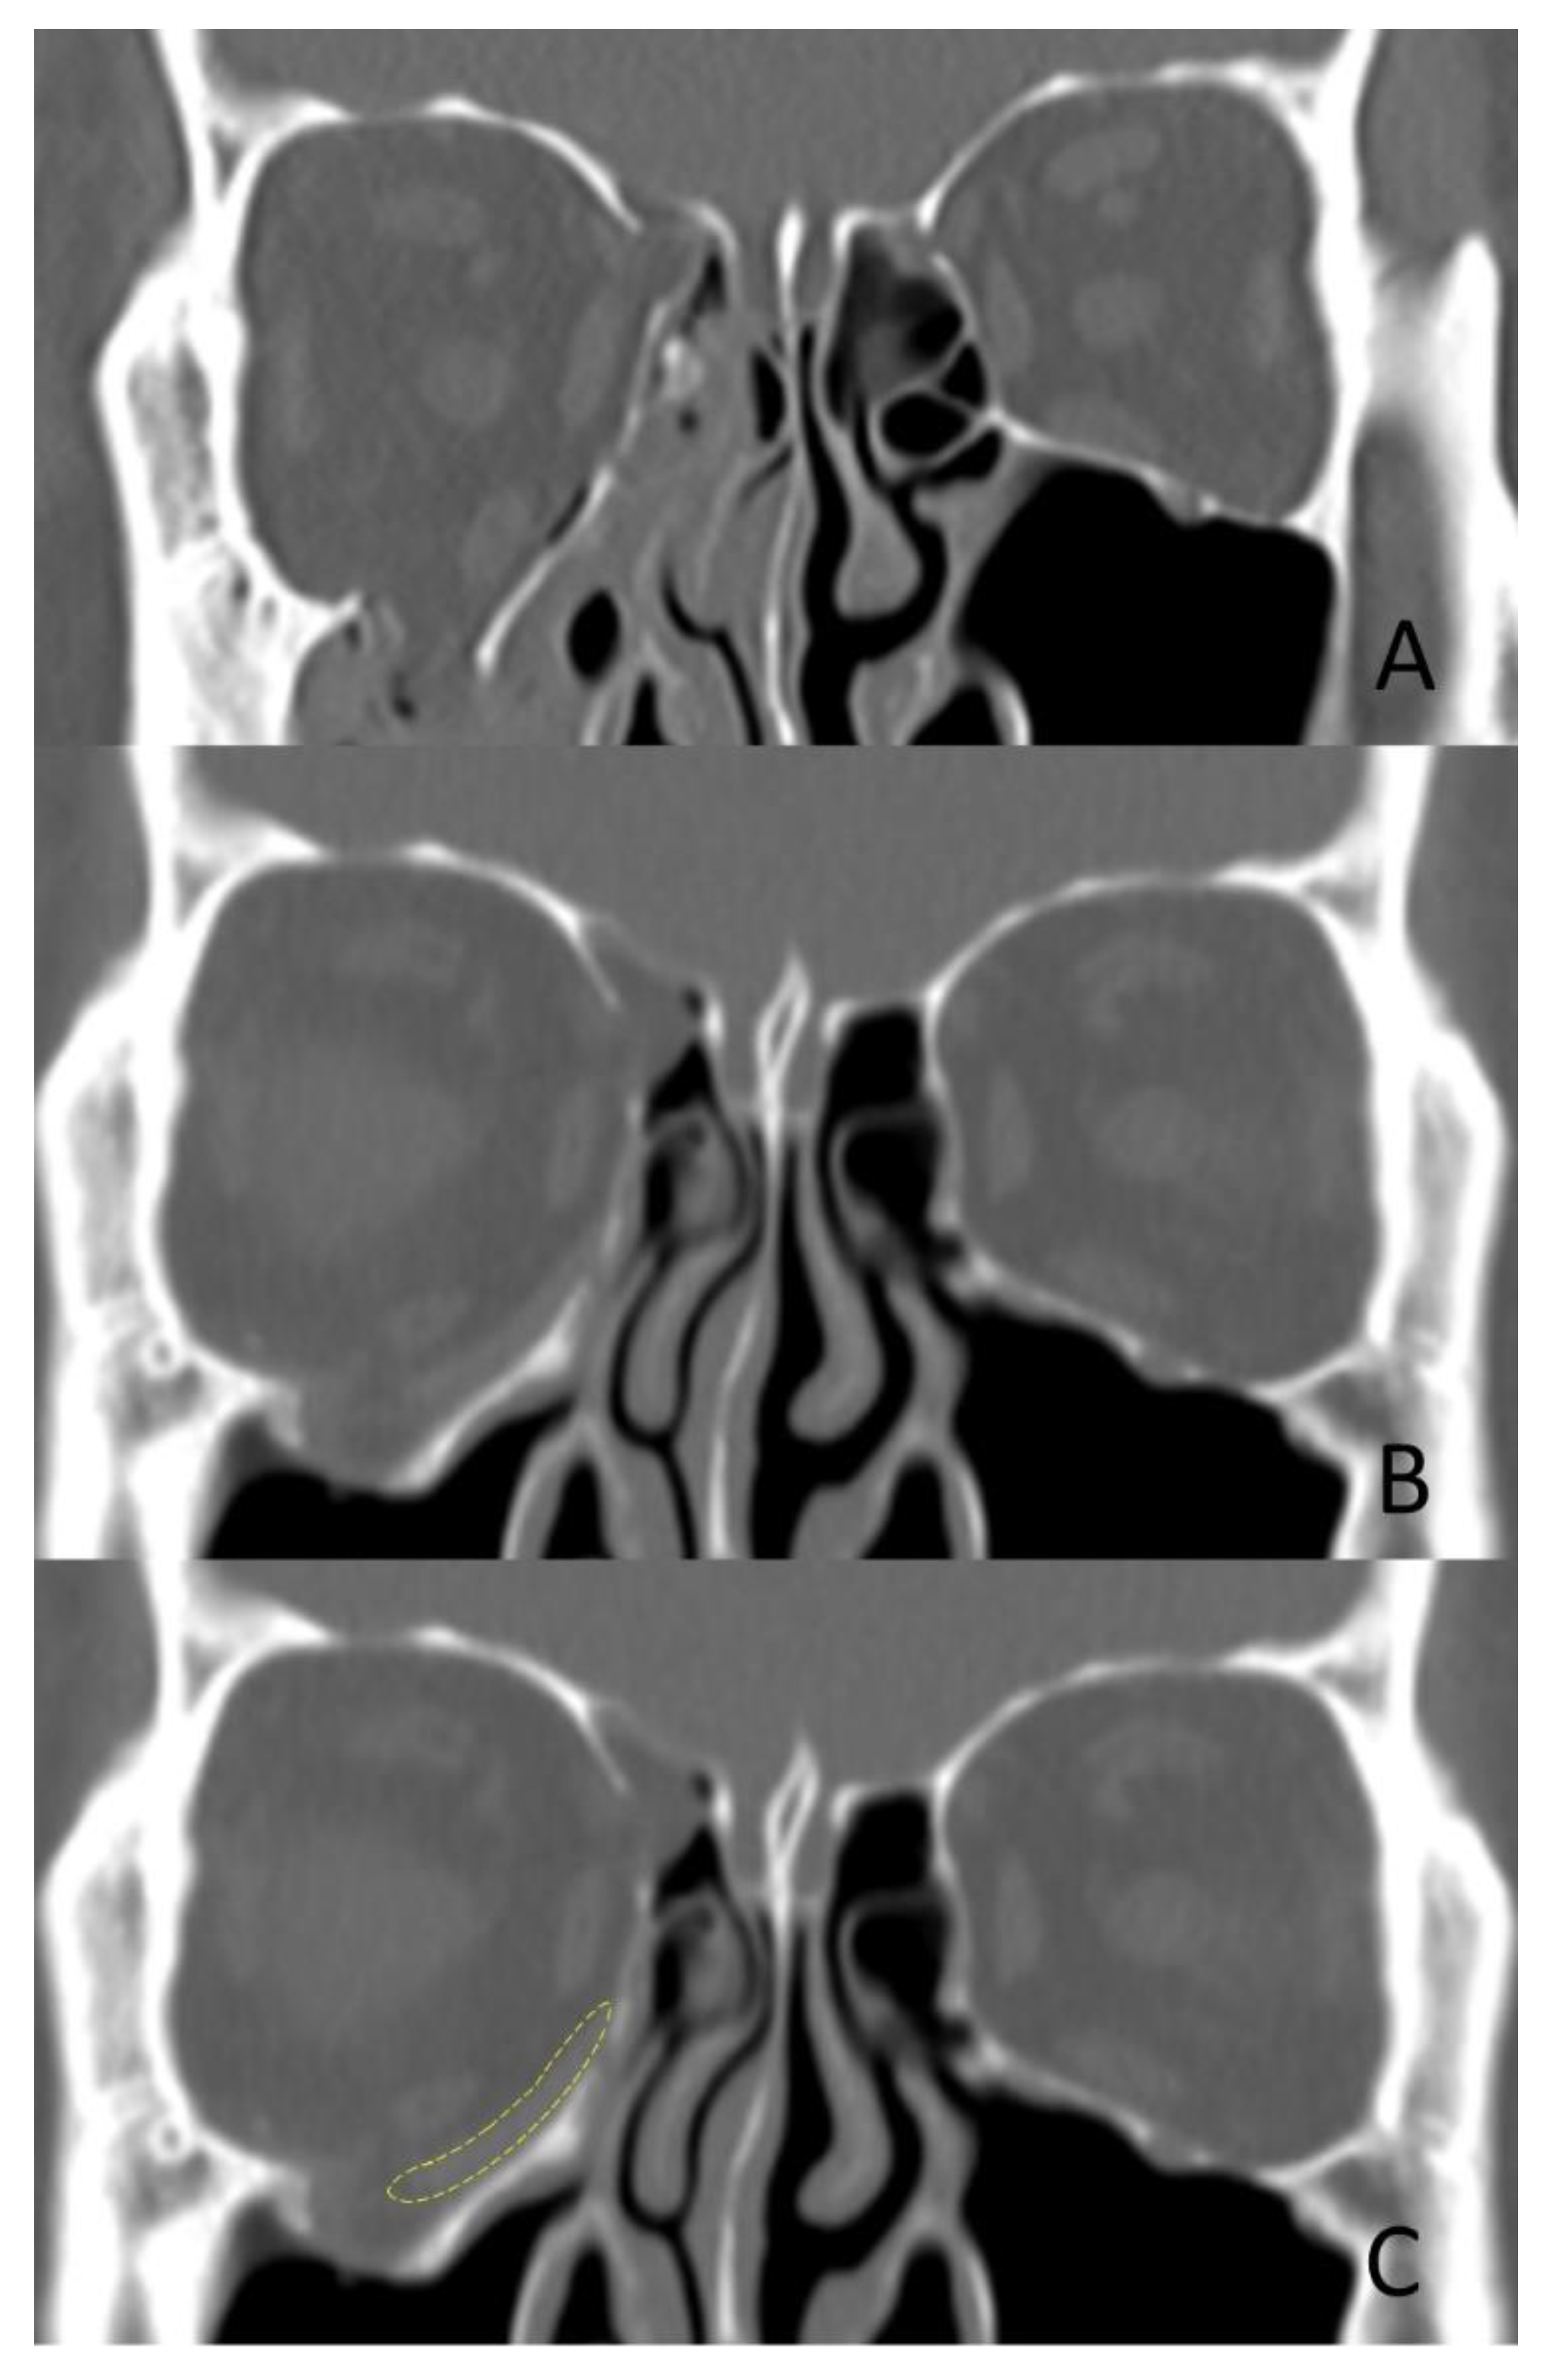

2.1. Fabrication of 3D-Printed Orbital Implant